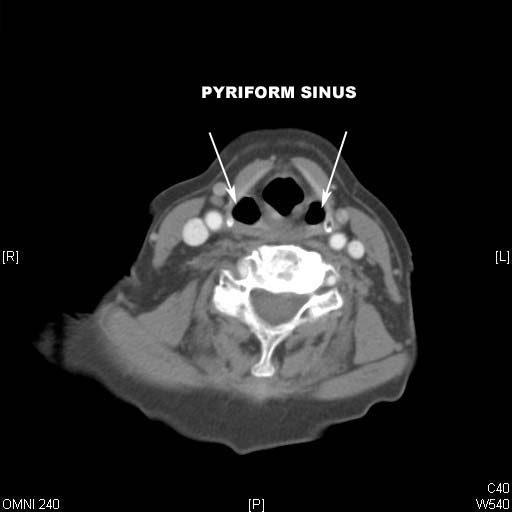

Identify Pyriform sinus